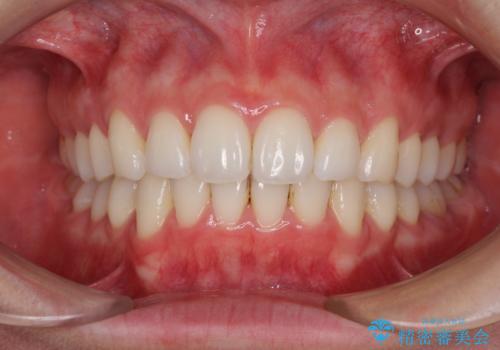

上顎歯列を遠心移動させたことで、前歯の叢生が解消されても前歯が前突することなく、左右ともに理想的な咬み合わせを達成することができました。